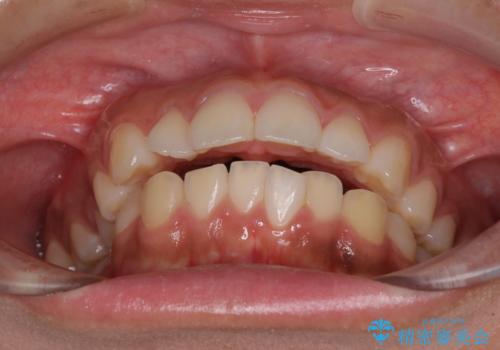

口が閉じられない 抜歯矯正で横顔の印象が劇的に変化

- 出っ歯と口の閉じにくさ、デコボコを気にして来院された患者様です。

口元の突出感を改善するため、上下左右第一小臼歯4本の抜歯を行い、ワイヤー装置による矯正治療を行うこととしました。

舌の突出癖により上下前歯は非接触であり、非常に前方に飛び出している状態でした。

舌のトレーニングをしっかりと行っていただき、口の閉じやすい歯並びに仕上げることができました。